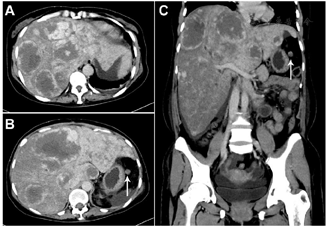

①腹部增强CT:肝脏多发低密度影,增强呈外周向内扩展的渐进性强化;脾脏明显肿大,增强呈渐进性的不均匀强化(图1,图2);诊断意见:考虑肝、脾血管源性肿瘤(血管瘤?血管肉瘤?)。

②18F-FDG PET/CT:脾脏明显增大,约23.1 cm×12.4 cm×24.5 cm,密度弥漫性减低,平均CT值约39 Hu,其内见多发条片状更低密度影,CT值约31 Hu,脾脏18F-FDG代谢不均匀性轻度增高,SUVmax=5.4;肝内多发类圆形低密度影,形态规则,边缘光整,最大者直径4.4 cm,密度均匀,平均CT值约42 Hu,病灶18F-FDG摄取均匀,与肝本底无差异,SUVmax=3.3(图1);诊断意见:巨脾伴18F-FDG代谢不均匀轻度增高,倾向恶性病变(原发);肝内多发低密度灶未见18F-FDG代谢异常,倾向良性病变(血管瘤)。